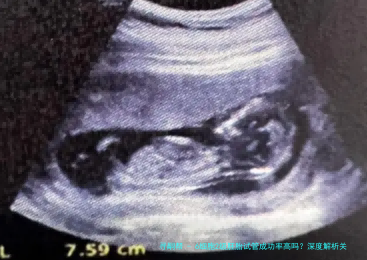

在试管婴儿治疗中,胚胎质量是决计成功率的核心因素。6细胞二级胚胎作为临床多见的中级质量胚胎,实际上际妊娠潜力备受留意。本文将从国际胚胎评介体系体例切入,结合最新临床数据,系统剖析该等级胚胎的着床规则及影响要点。

现行胚胎评估体系体例蕴藏细胞数、破裂均一性和碎片率三大维数。6细胞个体胚胎指受精卵形成后48-72小时形成6个完整细胞体,隶属于发育快慢正常的胚胎。二级评定标准为细胞大小轻度不均,碎片比率在10%-百分之二十五之间。这类胚胎虽非最优等级,但仍具有临床移植代价。